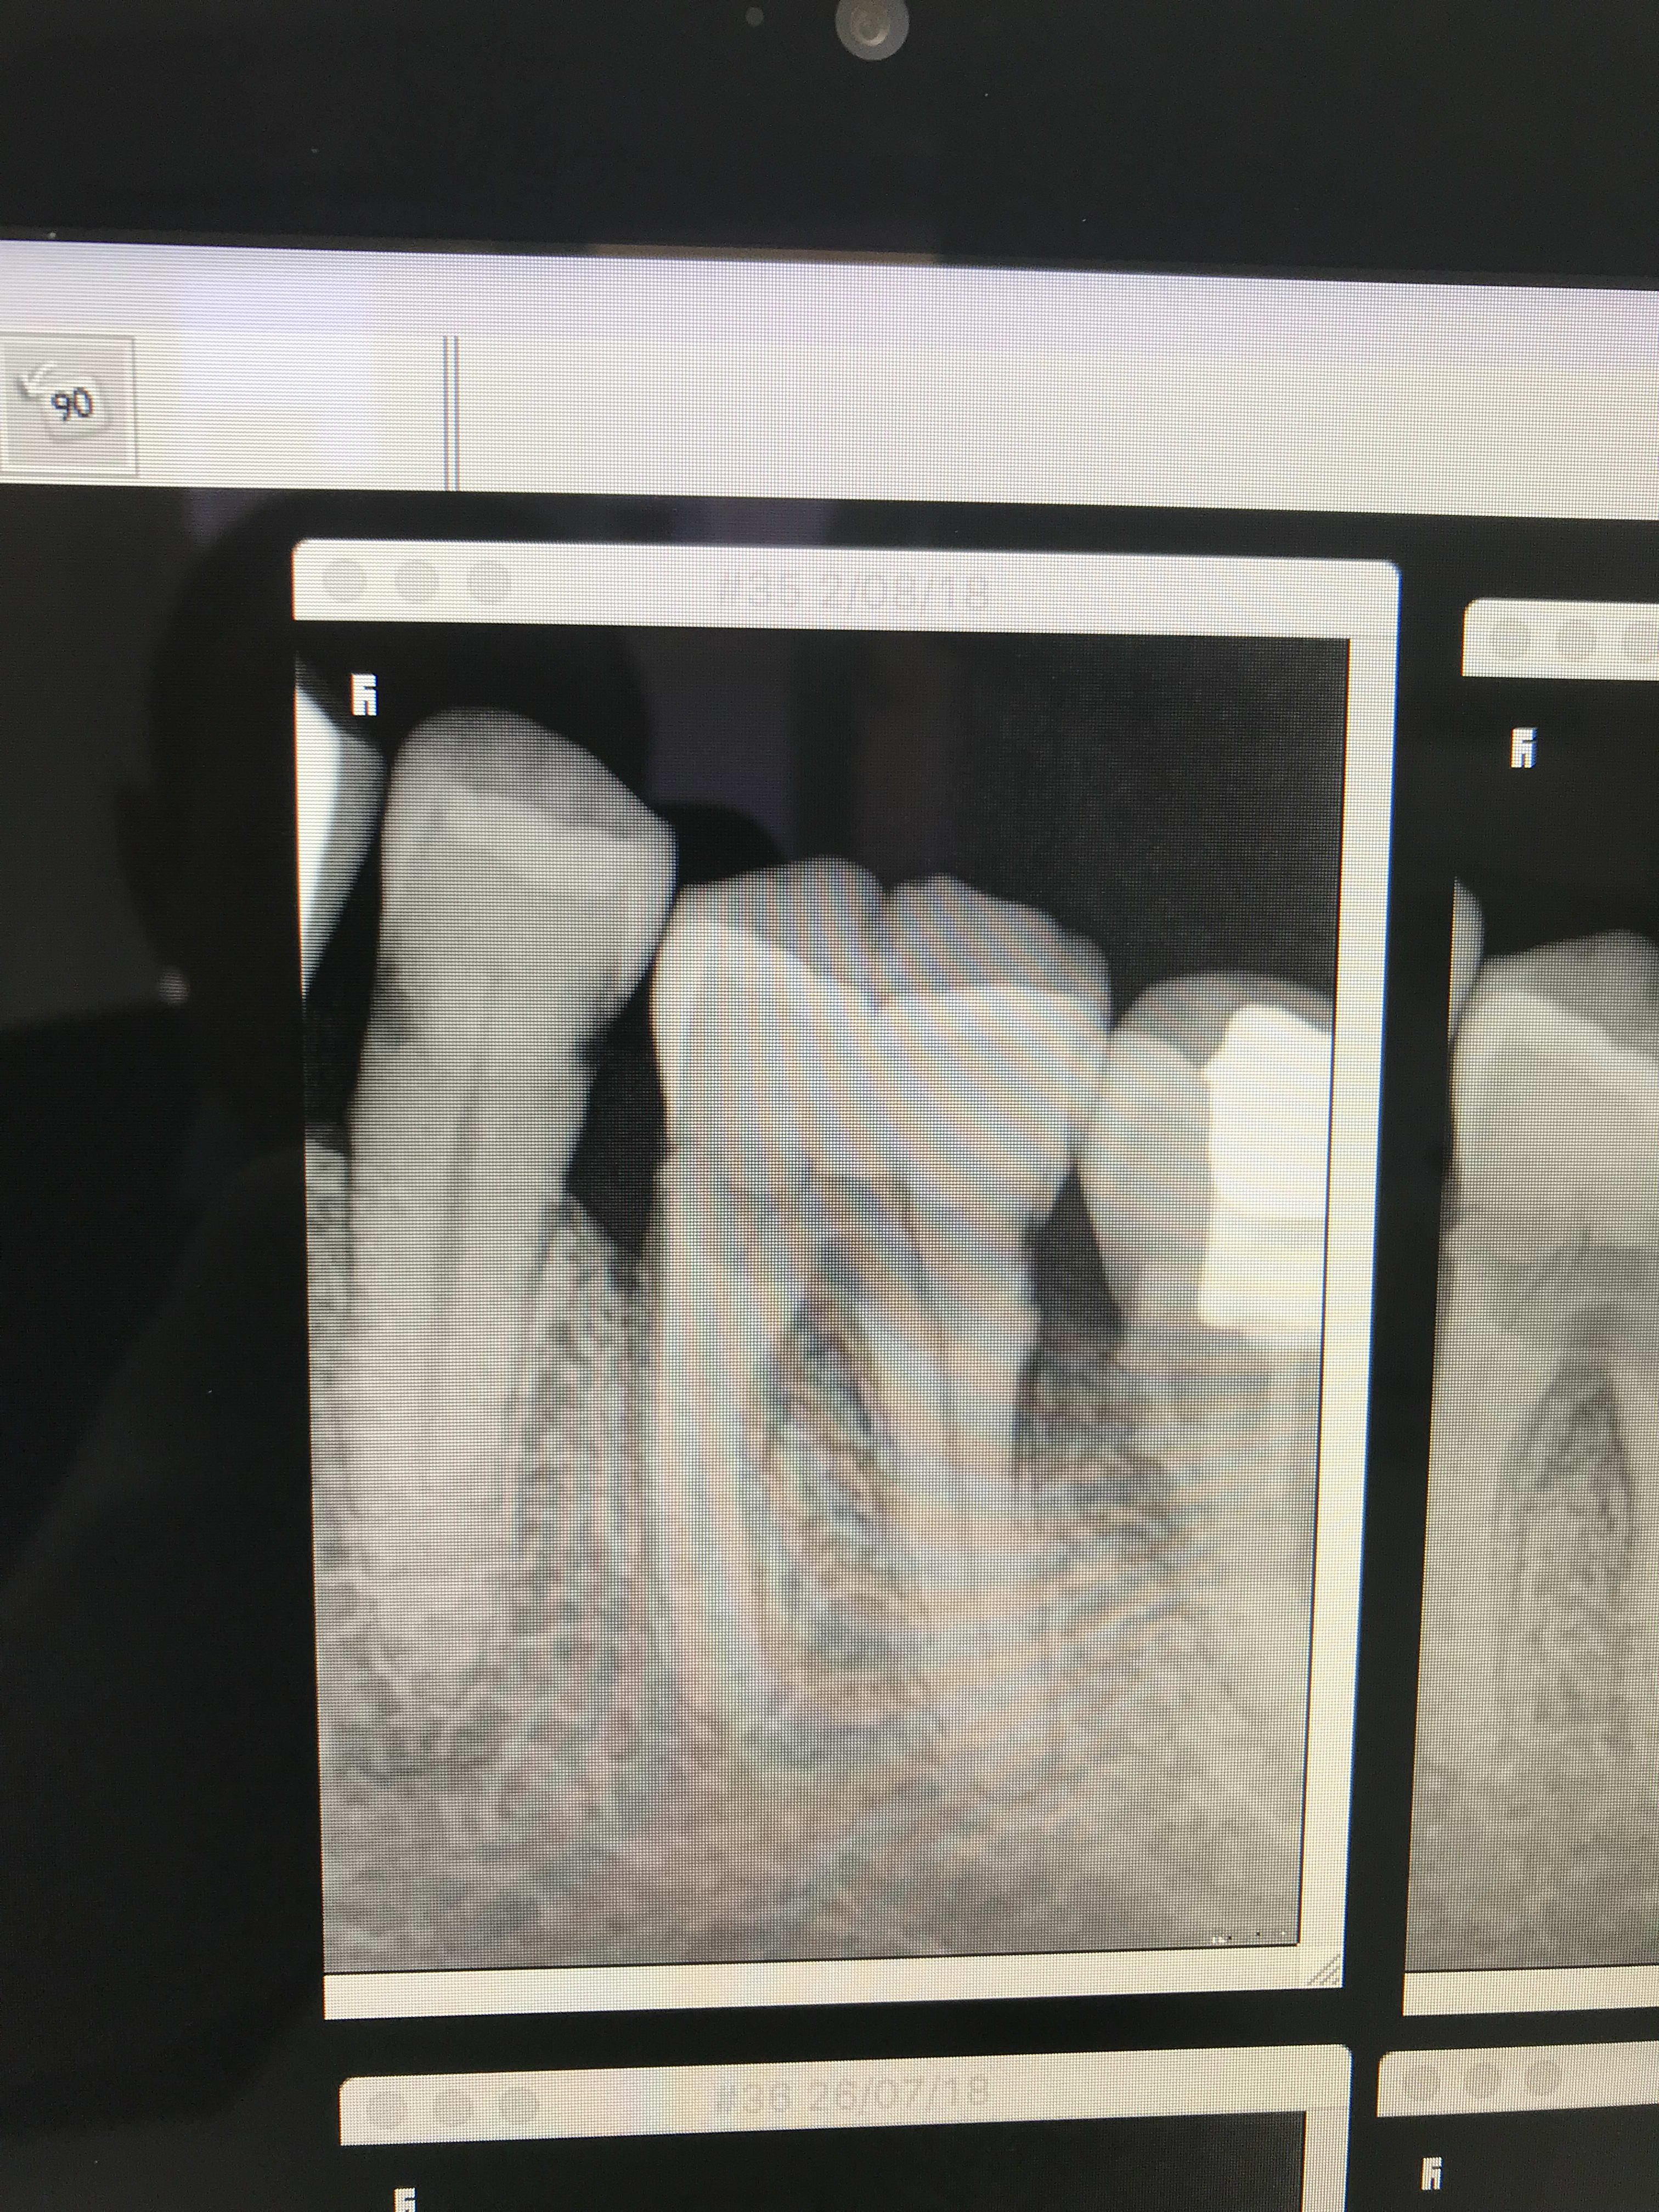

Comment traiteriez vous la 35

J’ai cette 35 avec 2 caries infra sous la jonction Email-cément,

Comment traiteriez vous ces lésions ?!

Merci pour vos réponses. Chicot, tu attaques les lésions par voie occlusale.... Sacré délabrement ? et c'est très infra... pour la 36, il y a un gros compo de collet, mais la lésion s'étend désormais en distale... Idem, je suis tiraillé par la couronne...

Hurluberlu, faire un collage si infra ? tu penses qu'avec la profondeur des lésions en direction pulpaire et vue qu'en sus, les lésions sont radiculaires, c'est jouable ?